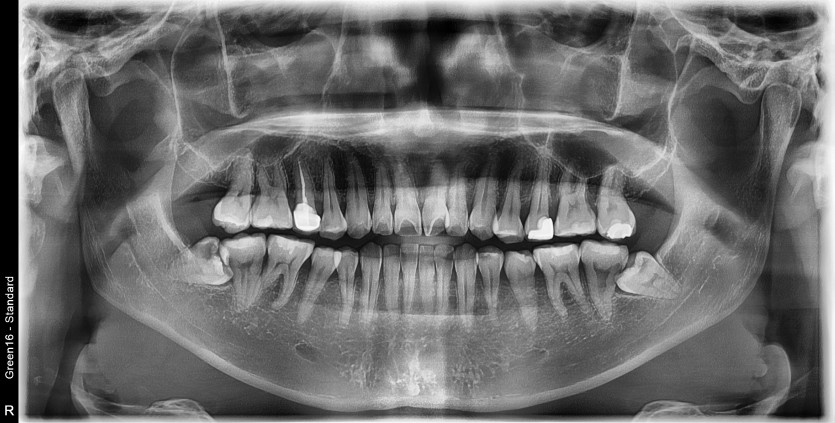

#48 사랑니 발치

구강 외과 전문의가 당일 발치했습니다.